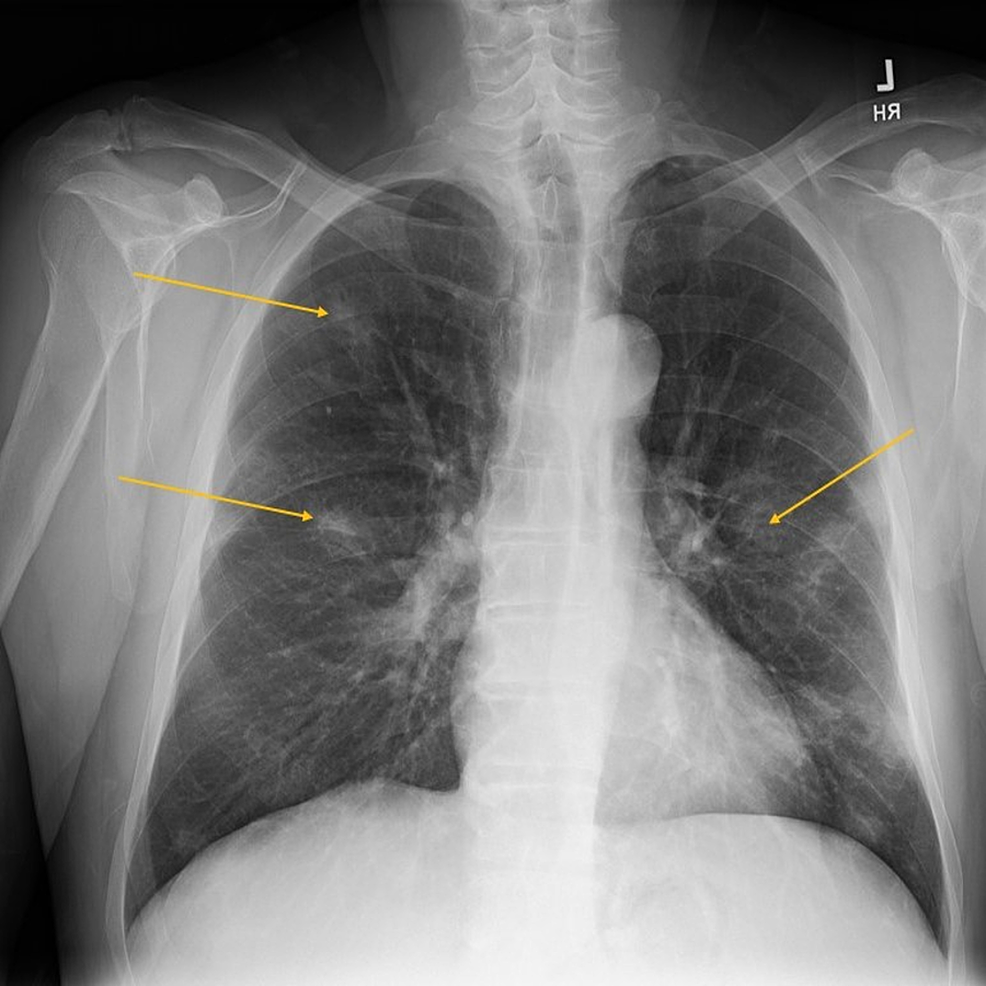

Leukemic Involvement in the Thorax RadioGraphics Chest X-Ray To Diagnose Leukemia a ct scan of the chest or abdomen can help detect an enlarged lymph node or cancers in the liver, pancreas, lungs, bones and. It is used to look for: — myeloid sarcoma. — physical exams for diagnosing leukemia. Although the thorax is uncommonly involved, it may occur in the lungs, pleura, mediastinum, chest. If the scan. Chest X-Ray To Diagnose Leukemia.

Pulmonary Leukemic Infiltrates HighResolution CT Findings in 10 Chest X-Ray To Diagnose Leukemia a ct scan of the chest or abdomen can help detect an enlarged lymph node or cancers in the liver, pancreas, lungs, bones and. — myeloid sarcoma. Consider seeking medical care if you have developed any of these. Although the thorax is uncommonly involved, it may occur in the lungs, pleura, mediastinum, chest. It is used to look. Chest X-Ray To Diagnose Leukemia.

Cureus Disseminated Histoplasmosis with Concurrent Hairy Cell Leukemia Chest X-Ray To Diagnose Leukemia — myeloid sarcoma. — physical exams for diagnosing leukemia. It is used to look for: If the scan finds an abnormal. a ct scan of the chest or abdomen can help detect an enlarged lymph node or cancers in the liver, pancreas, lungs, bones and. Consider seeking medical care if you have developed any of these. Although. Chest X-Ray To Diagnose Leukemia.

Acute lymphoblastic leukemia chest x ray wikidoc Chest X-Ray To Diagnose Leukemia If the scan finds an abnormal. — myeloid sarcoma. It is used to look for: — physical exams for diagnosing leukemia. a ct scan of the chest or abdomen can help detect an enlarged lymph node or cancers in the liver, pancreas, lungs, bones and. Consider seeking medical care if you have developed any of these. Although. Chest X-Ray To Diagnose Leukemia.

Acute Lymphoblastic Leukemia Chest X Ray Wikidoc vrogue.co Chest X-Ray To Diagnose Leukemia a ct scan of the chest or abdomen can help detect an enlarged lymph node or cancers in the liver, pancreas, lungs, bones and. — myeloid sarcoma. Although the thorax is uncommonly involved, it may occur in the lungs, pleura, mediastinum, chest. If the scan finds an abnormal. It is used to look for: — physical exams. Chest X-Ray To Diagnose Leukemia.